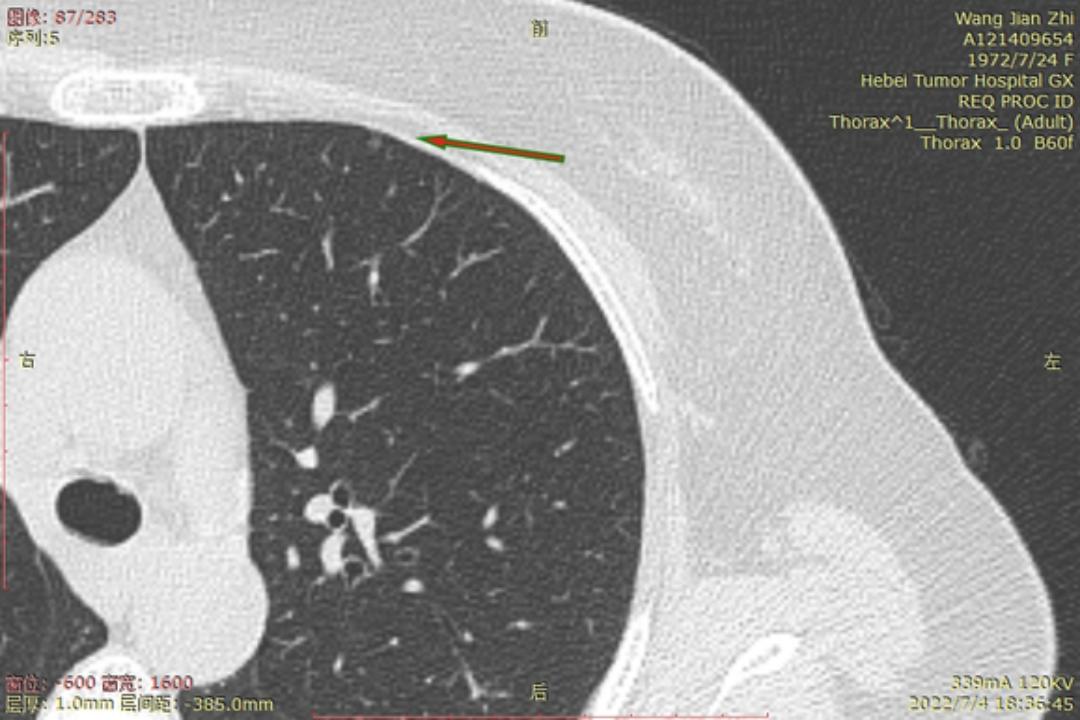

今年6月22号河北省人民医院进行CT检查后,报告双肺多发磨玻璃结节及微小结节以右肺为多,建议六个月后复诊。我于7月3号在河北省四院胸外科就诊,大夫建议复查薄层CT,7月4日CT结果报告示两肺多发结节,部分为磨玻璃密度,建议三个月复查,省四院的主任看了CT后有的建议立即住院手术,有的建议三个月复查,专家意见不一致,后来我看了主任的贴吧,首次发现肺结节先口服莫西沙星,三个月后再复查的贴吧,就没有立刻手术,从7月4日开始口服莫西沙星,现已完成15天疗程。等待复查的这一段时间里,总是担心大的结节已有浸润,请主任给予帮助,看看我的CT,给出我治疗建议,麻烦主任了!

结1